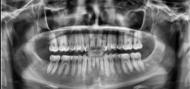

En la radiografía lateral de cráneo ( Figura 6 ) se ve la línea estética de Rickets, que el labio superior se encuentra a +0.5 mm y el inferior a -2 mm. En las mediciones cefalométricas más importantes en la figura 11 un ANB de 5º, GoGn-SN de 33º y FMA de 21º crecimiento normodivergente y Witts de -1 mm. A los criterios dentales encontramos

1-PLT de 129º e IMPA 99º proinclinación de incisivos tanto superiores como inferiores. En la radiografía panorámica (Figura 7), la presencia de 32 órganos dentarios, con terceros molares inferiores aún sin erupcionar y terceros molares superiores

7. Radiografía panorámica.

ya erupcionados, falta de paralelismo radicular, asimetría condilar, articulación temporomandibular (ATM) izquierda afectada.

Secuencia de radiografías laterales de cráneo (Figura 15) vemos que el ANB disminuyo 1º de inicio a fin clase I con tendencia a clase II esquelética a final. Reducción de Witts 0.5 mm final, crecimiento normodivergente. Mandíbula más pequeña que el maxilar, cambio por el avance mandibular.

Panorámicas de inicio a fin (Figura 16) el paralelismo radicular, genera estabilidad a largo plazo en el tratamiento. Se extrajeron los terceros molares para eliminar discrepancia posterior y lograr adecuada

Figura 16. Radiografías panorámicas. a) Inicio. b) Progreso. c) Final.